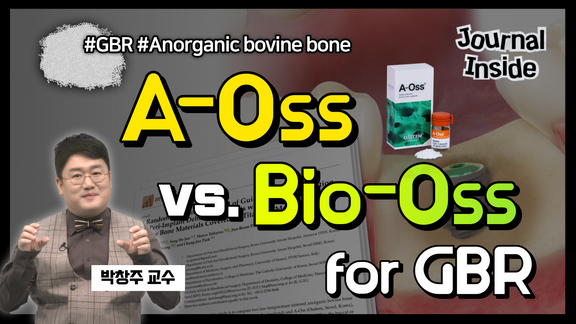

A Randomized controlled trial of guided bone regeneration...

Journal Inside

2024-04-18T00:00